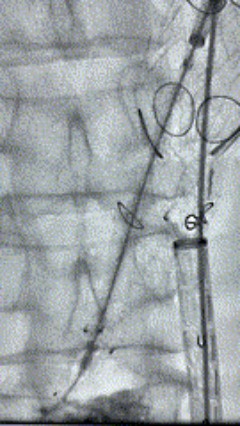

2. 左侧肱动脉入路,超选至降主动脉,更换8F-900mm长鞘,造影提示IV型胸腹主动脉瘤,累及双肾动脉。

3. 经右股动脉导入超硬导丝,然后导入先健G-Branch 胸腹主动脉主体覆膜支架TAAA3418120e7i1010 一枚,释放主体支架至内分支打开,然后经左侧肱动脉入路,抓捕预置导丝成功后,将长鞘进入内分支出口处。

4. 经长鞘导入导管后,超选入腹腔干动脉,送入先健覆膜支架10*80mm一枚,近端重叠内分支,远端重叠腹腔干动脉,并予以10mm球囊后扩,手推造影显影良好。

5. 撤出腹腔干导丝导管,经左肱动脉长鞘继续抓捕预置导丝将长鞘超选至另一侧内分支,后超选进肠系膜上动脉,沿导丝送入先健覆膜支架10*100mm一枚,近端重叠内分支,远端重叠于肠系膜上动脉,并予以10mm球囊后扩,手推造影显影良好。